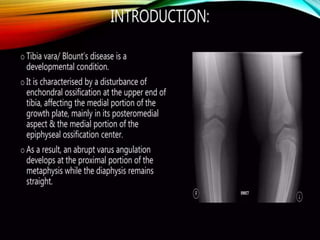

HISTORICAL BACKGROUND

• ERLACHER (1922) –first description of tibia

vara and internal rotation

• Walter BLOUNT(1937)-described tibia vara

Blount:

• An osteochondrosis similar to coxa plana and

madelung deformity but located at the medial

side of proximal tibial epiphysis